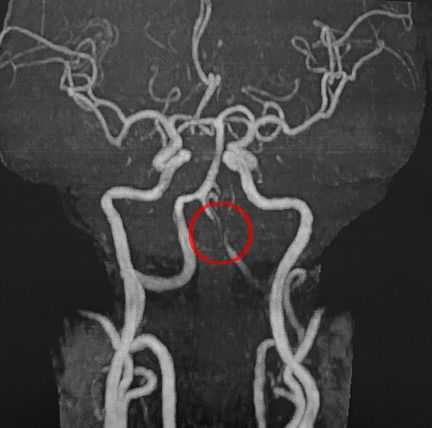

椎骨動脈に異常所見が見られます。

これは血の流れを映す撮影方法です。

今度は血管の太さがわかる撮影方法で確認します。

分岐部分に、狭まりと膨らみが見受けられます。

椎骨動脈解離の症状です。

さらに別の撮影方法で出血の有無を確認しましたが

画像上、出血は確認できませんでした。